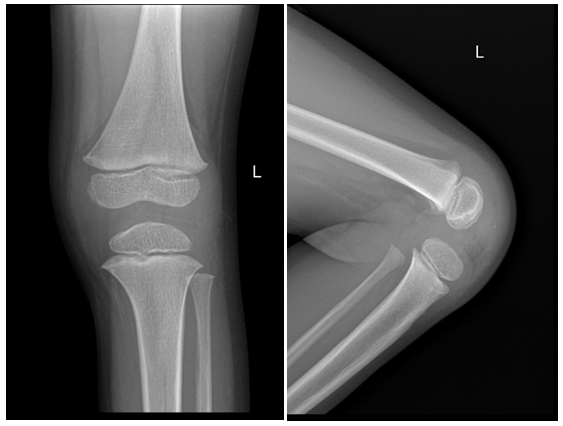

As part of primary survey patient’s chest and pelvis X-rays done at trauma bay shows no abnormality. AP and lateral X-rays of left femur showing hip and knee joints were reviewed by different ranked orthopaedics surgeons with agreement of normal x-ray impression (Figure 1 & 2). The following visits for the same complain has different x-rays with same impression of normal x-ray (Figure 3). Except for the one at last visit with the clinical evidence of deformity, patient has diaphysial femur fracture (Figure 4 ).

Figure 4 X ray showing diaphysial femur fracture.

Patient discharged with diagnosis of contusion. Patient visited emergency department in two consecutive days with the same complain of left thigh pain at even at rest and inability to bear weight where he were evaluated by different orthopaedic surgeons and has same impression of contusion. At third visit patient brought by family with deformed left thigh after unattended incident at home.